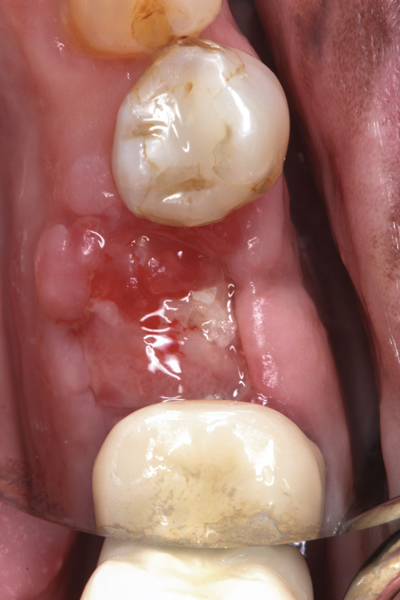

The four presented cases shown in Figure 1 through Figure 25 were all treated in a similar manner as outlined in detail in the captions for the first case (Figure 1 through Figure 11). In all four cases, teeth with pathosis were removed, buccal and lingual flaps were elevated, and sites were surgically debrided. A Cytoplast d-PTFE barrier was sized and inserted usually under the buccal flap, the bone graft was added, the barrier was then tucked under the lingual flap, and the flaps were sutured. Bone grafts were used in all of the cases, because buccal bony plates were resorbed and the bone graft helped support the barrier.

Fig 17. Bone graft was placed in the socket and a d-PTFE barrier was used to cover the graft. The bone graft material was placed beyond the alveolar housing to accommodate shrinkage of graft material and to facilitate attaining a wide alveolar ridge. The barrier was removed after 6 weeks.

Figure 17

Fig 18. Healed ridge exposed after 6 months.

Figure 18